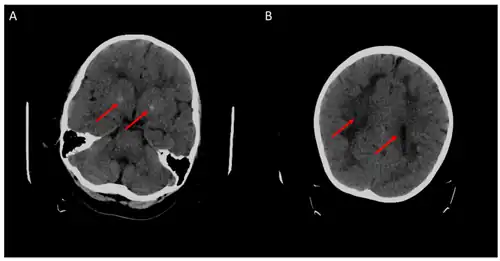

![]() | |

| 5-methyltetrahydrofolate is decreased in concentration in the human brain | |